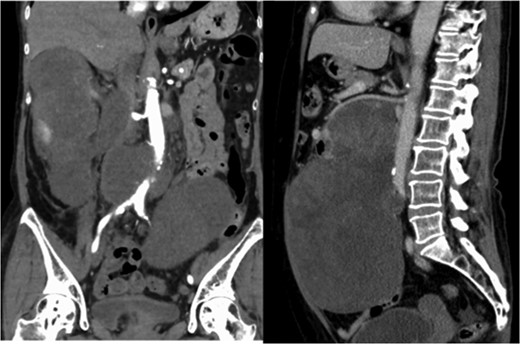

A 60-year-old female visited a clinic because of abdominal distension. She noticed abdominal distention one year prior to her clinical visit, but she left it for a year. Gradual enlargement of the mass eventually made her decide to see a doctor. Enhanced abdominal computed tomography (CT) revealed large retroperitoneal tumors. Mini-laparotomy and tumor biopsy confirmed her diagnosis as dedifferentiated liposarcoma, then she was referred to us for further examination and treatment. A multidetector CT scan revealed a hypodense mass in the retroperitoneum, with a size of ~30 × 20 cm2. The tumor appeared to invade the duodenum, head of the pancreas, right kidney, IVC and abdominal aorta (Fig. 1). The IVC was almost occluded by the tumor, but venous return from the lower extremities beyond the tumor was observed through collateral veins around the tumor (Fig. 2). The tumor invaded the abdominal aorta just below the left renal artery to the common iliac artery bifurcation, although the root and entire length of SMA appeared to be free from the tumor (Fig. 3). She underwent en bloc resection of the RL with resection of the right kidney, duodenum, head of the pancreas, a portion of the inferior IVC and abdominal aorta. Ax-F & F-F bypass was performed for vascular reconstruction using poly-tertrafluoroethylene (PTFE) to maintain the blood flow to the both lower extremities (Fig. 4). The lower abdominal aorta and both sides of common iliac arteries were resected with the tumor. The proximal stump of the abdominal aorta was closed with a running suture and covered by the omentum. The IVC was resected from just below the left renal vein to the common iliac veins. Reconstruction of the venous system including IVC and common iliac veins was not performed because venous collateral pathways had already developed sufficiently. Child’s reconstruction was performed after pylorus-preserving pancreatoduodenectomy. The duration of the surgery was 19 h 22 min, and blood loss was 4 811 mL, requiring 1680 mL of red blood cell transfusion. The tumor was 33 × 20 × 13 cm3 in size, weighed 4800 g, and had a fibrous capsule (Figs 5 and 6). Pathological examination revealed a dedifferentiated liposarcoma with negative margin (Fig. 7). Tumor invaded the pancreatic capsule, the renal capsule, the adventitia of the IVC and the abdominal aorta and infiltrated into the muscularis propria and focally into lamina propria of the duodenum. Edema of the both lower extremities was noted as postoperative complication, but that was gradually resolved by diuretics. The patient was discharged 37 days after surgery without serious postoperative complications such as pancreatic fistula, as well as graft infection or obstruction of two bypasses. Currently, she remains alive and well with no evidence of recurrence at 16 months post-operation.

Multidetector CT scan (coronal view and sagittal view). The tumor surrounded the abdominal aorta from the superior mesenteric artery orifice to the common iliac artery bifurcation.